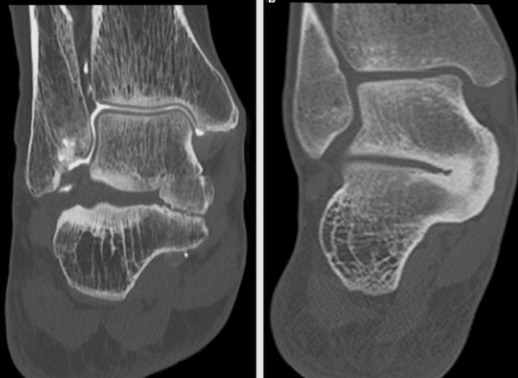

Coalitions tarsiennes

2. Synostose talo-calcanéenne